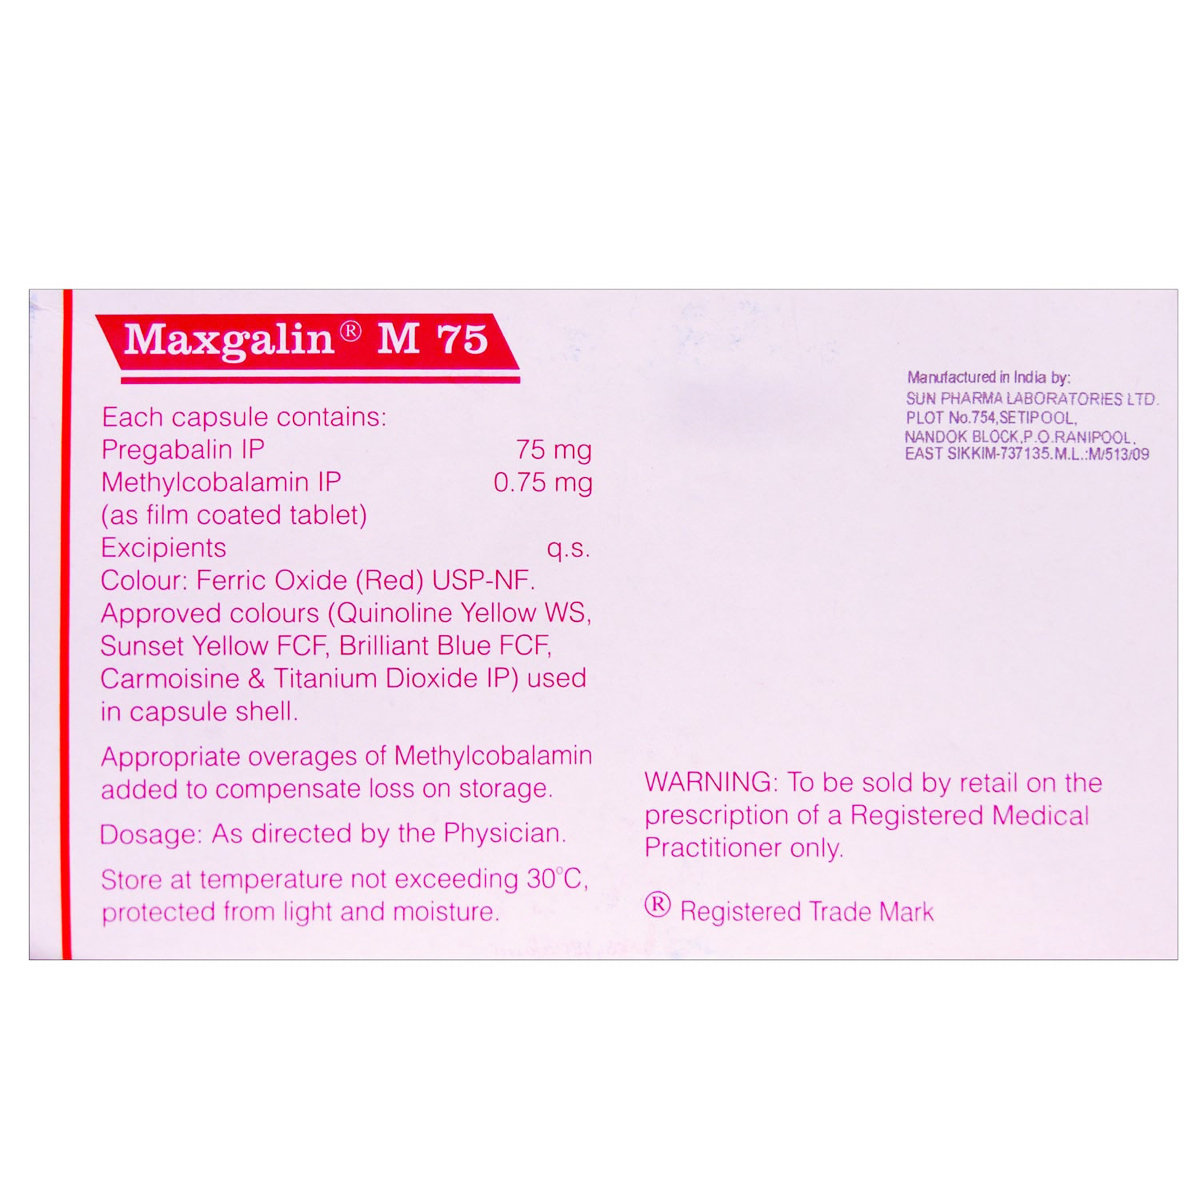

Maxgalin M 75 Capsule 10's

₹41.6 Cashback (15%)

Maxgalin M 75 Capsule is used in the treatment of neuropathic pain. It contains Pregabalin and Methylcobalamin, which decreases the pain signals and helps rejuvenate and protect damaged nerve cells. It may cause common side effects such as dizziness, drowsiness, headache, loss of appetite, nausea or vomiting, diarrhea, headache, vision problems, and sweating. Before taking this medicine, you should tell your doctor if you are allergic to any of its components or if you are pregnant/breastfeeding, and about all the medications you are taking and pre-existing medical conditions.

Maxgalin M 75 Capsule is a combination of two medicines: Pregabalin and Methylcobalamin. Pregabalin acts by decreasing the pain signals sent by a damaged nerve in the body. On the other hand, Methylcobalamin helps rejuvenate and protect damaged nerve cells by producing a substance called myelin (outer protective layer of nerve cell - neuron).

Medicinal Benefits

Maxgalin M 75 Capsule is a combination of two drugs: Pregabalin and Methylcobalamin. Pregabalin is an anticonvulsant that affects the brain's chemicals that send pain signals across the nervous system. It works by binding to the specific site on voltage-gated calcium channels (responsible for excitatory response), thereby decreasing brain activity. This effect helps in relieving nerve pain and lowers the risk of seizures. On the other hand, Methylcobalamin is a form of vitamin B12 that helps rejuvenate and protect damaged nerve cells by producing a substance called myelin (outer protective layer of nerve cells). Together, Maxgalin M 75 Capsule helps in providing relief from neuropathic pain and improved nerve signal conduction.